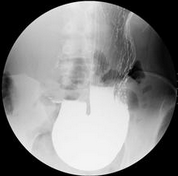

胃下垂是指站立时,胃的下缘达盆腔,胃小弯弧线点降至髂嵴连线以下,胃下垂是胃气严重受损的表现,轻度患者多无症状,中度以上者会常出现胃肠动力差、消化不良的症状,长期胃下垂者常有消瘦、乏力、站立性昏厥、低血压、心悸、失眠、头痛等症状,医师表示,胃下垂是亚健康的严重阶段,要及时治疗。那么,胃下垂还有哪些症状呢?下面福州台江医院胃肠医师为我们讲解胃下垂的症状及治疗。